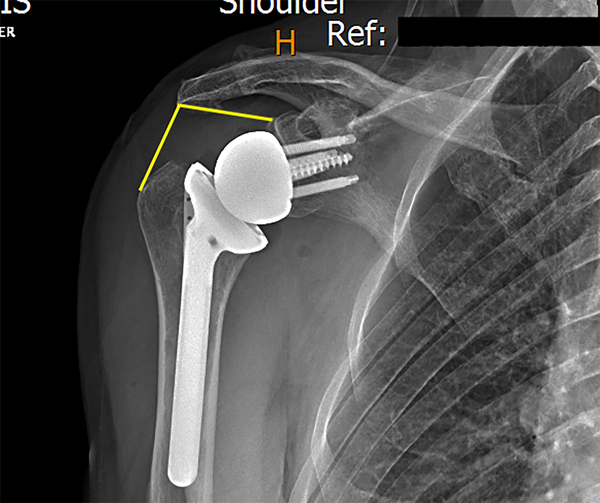

En todos los pacientes se realizó una radiografía postoperatoria con una proyección lateral y AP verdadera de hombro para evaluar las mediciones radiográficas de acuerdo a lo descripto por Boutsadis.6 El LSA fue medido desde el punto más superior y lateral del tubérculo glenoideo, el punto más lateral del acromion y el borde más lateral de la tuberosidad mayor (fig. 1). El DSA fue tomado desde el punto más lateral del acromion el tubérculo glenoideo y el borde más superior de la tuberosidad mayor (fig. 2). Para evaluar la reproducibilidad de las mediciones, estas fueron tomadas por tres de los autores (un médico general, un cirujano de hombro, un fellow en cirugía de hombro) y se evaluó la concordancia entre ellos.

Figura 1: Medición de ángulo de lateralización.